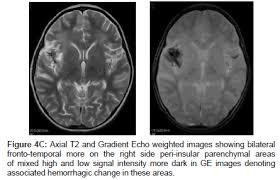

Watershed distribution ischemia in areas remote from the primary herpetic lesions may be seen. Herpes simplex encephalitis typically manifests in older adults (about 50% of cases) with headache, fever, altered sensorium, and even seizure. Hippocampus, temporal lobe, and the ponsfigure 4a.7. Herpes simplex virus (hsv) is the most common cause of acute fatal sporadic encephalitis, with a particular predilection for the limbic system. Unfortunately, the imaging findings are often nonspecific with overlapping appearances. This lesion was seen in all patients as the disease progressed. Severe edema, petechial hemorrhage, and massive hemorrhagic tissue necrosis can be seen on gross specimens. He was managed with intravenous acyclovir 30mg/kg and supportive therapy. that appeared in a recent issue of clinical infectious diseases. However, mimics of hse, including other infections and increasingly recognized autoimmune causes, have been described in cases of tl encephalitis. But changes are not specific for hsv (e.g. The characteristic feature of hse is hemorrhagic necrosis of the temporal lobe. The basal ganglia are usually spared.

Herpes simplex (hsv) encephalitis is the most common cause of fatal sporadic fulminant necrotizing viral encephalitis and has characteristic imaging findings. Metabolic, vascular, neoplastic, infective and paraneoplastic diseases. A 40‑year‑old male patient with herpes simplex virus encephalitis presented with altered sensorium. Key imaging features include bilateral or unilateral signal abnormality in the temporal lobes that extends to the limbic system, early hemorrhagic changes, restriction on dwi, and abnormal enhancement. Mri revealed hyperintensities on t2 weighted images in both frontal and temporal lobes suggestive of herpes simplex encephalitis (fig 1).

A feasibility study of quantifying longitudinal brain changes in herpes simplex virus (hsv) encephalitis using magnetic resonance imaging (mri) and stereology. In the present study, flair bth was most frequently seen in patients with hsv encephalitis. Mri is the diagnostic modality of choice abnormal in 90%; Herpes simplex virus (hsv) encephalitis hsv encephalitis (hsve) is the most common cause of infectious encephalitis (1); The basal ganglia are usually spared. Encephalitis, magnetic resonance imaging, meningoencephalitis, viral. that appeared in a recent issue of clinical infectious diseases. Although far less common, essentially any part of the central nervous system can be involved 9. 1 mri t2 weighted image, showing bilateral temporal lobe hyperintensities. However, mimics of hse, including other infections and increasingly recognized autoimmune causes, have been described in cases of tl encephalitis. Two subtypes are recognized which differ in demographics, virus, and pattern of involvement. Because early diagnosis is possible in more cases of herpes simplex encephalitis (hse) as a result of the high sensitivity of mri, now widely available, a larger number of patients are receiving appropriate treatment with iv acyclovir. Limbic encephalitis, mca ischaemia, tumours, effects of seizures) hyperintense t2 signal in the medial temporal lobes, inferior frontal lobes and insula basal ganglia are usually spared